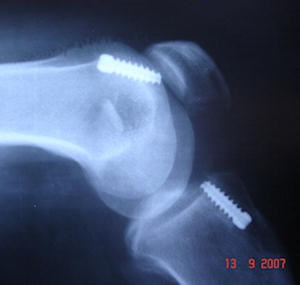

Planlamada önceki kesiler, kullanılan implantlar, ilk tünellerin yeni açılacak tünellerle ilgisi değerlendirilmeli, ilk implantların çıkartma setleri bulundurulmalıdır. İlk tüneller çok genişlemiş ve yeni greftin yerleşimini ve tespitini engelliyorsa iki seanslı cerrahi gerekli olabilir. İlk seansta implantlar çıkartılır ve tüneller greftlenir, sonra ikinci seansta revizyon cerrahisi yapılır. Bunun için oto veya allogreft hazırlığı olmalıdır. Revizyonda kullanılacak tendon grefti seçimi önemlidir. Hastada daha önce kullanılmayan otolog greft kaynakları ilk tercih olmalıdır. Bu mümkün değilse karşı diz ya da allogreft tercih edilebilir.Cerrahi teknik

Revizyon cerrahisi diz ekleminin artroskopisi ile başlar. İlk cerrahideki greft artıkları temizlenir, eşlik eden meniskal ve kondral patolojiler düzeltilir. İlk cerrahi sırasında kullanılan implantlar, yeni tünelleri engellemiyorsa çıkartılmamalıdır. Özellikle yeni tünele yakın olan implant çıkartılırsa, tünel duvarları zayıflayabilir. Tibial tarafta çoğunlukla daha medialden bir tünel açılabilir.

Tünel genişlemesi varsa, büyük kemik bloklu allogreft veya greftleme sonrası iki seanslı cerrahi düşünülmelidir. Femoral tünel ilk cerrahide çoğunlukla önde açıldığı için arkaya ve inferiora doğru ikinci bir tünel mümkündür. Standart tespit yöntemlerine ek olarak eklemden uzak ilave tespit yöntemleri gerekli olabilir. Genişlemiş tünellerde eklemden uzak tespit yapılırsa, tünel içinde hareketi azaltmak için biyoçözünür vida veya kemik grefti eklenebilir.